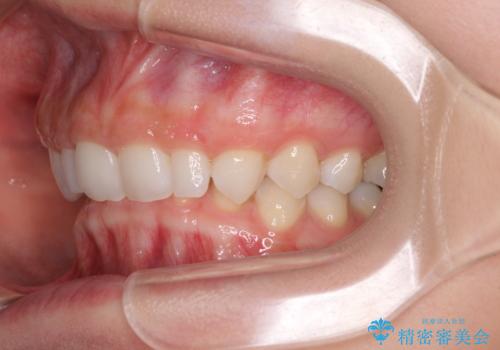

前歯のデコボコと小さい歯を改善 インビザラインとオールセラミッククラウン

- 前歯のデコボコと左右の矮小歯を気にして来院された患者様です。

矮小歯の前後にスペースを作るようにインビザライン矯正治療を計画し、矯正治療後にオールセラミッククラウンによる補綴治療を行うこととしました。

アンカースクリューを用いて上顎歯列全体を後方移動させ、極力過蓋咬合も改善されるよう計画しました。

インビザラインは長時間装着を自己管理する必要がありますが、残念ながら十分な時間の装着を行うことができませんでした。

何とか矮小歯を改善するスペースを作ることはできましたが、過蓋咬合を改善するには至りませんでした。